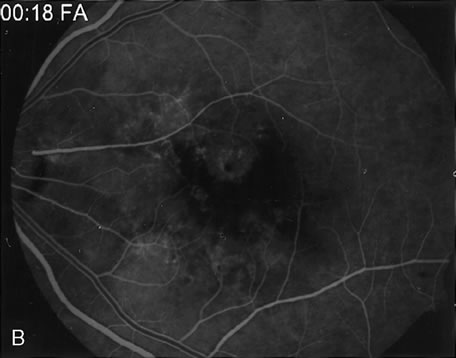

DIAGNOSIS Trauma can induce a wide spectrum of alterations of the retina, RPE, and choroid. Most types of traumatic maculopathy, such as Purtscher's retinopathy, Berlin's edema, retinal contusion, traumatic macular hole, and choroidal rupture, are readily apparent on clinical examination.257 Choroidal rupture, althoughe usually evident clinically, may be more obvious on FA (Fig. 39). Contusion necrosis of the RPE may present clinically with an associated RPE detachment, an overlying neurosensory detachment, and a subtle change in RPE pigmentation. FA can demonstrate the site of leakage into the subretinal space, unless the RPE defect has healed by the time of testing. FA is particularly helpful in differentiating retinal concussion (Berlin's edema), in which FA findings are normal, from retinal contusion, in which there is RPE damage and, consequently, increased transmission of choroidal fluorescence on FA.257 In Purtscher's retinopathy, FA can document vascular closure, which accounts for the retinal infarctions (Fig. 40).258